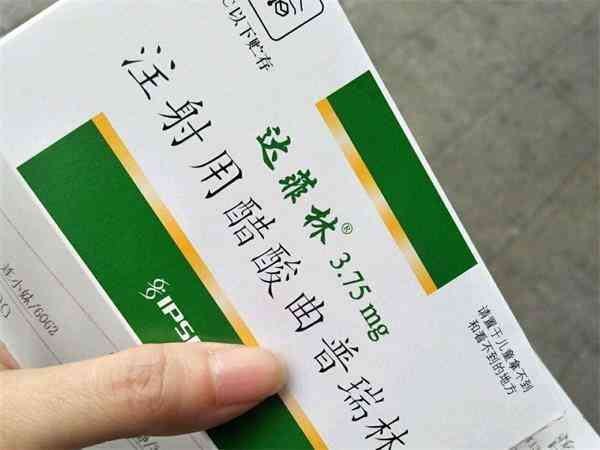

浅谈打达菲林降调针的位置,到底是哪个部位一看便知

达菲林降调针在试管婴儿的临床应用上是比较常见的,它的注射方式是肌肉注射,大部分女性患者在做试管婴儿的时候都是采用的是臀大肌注射,但也有采用三角肌和肱二头肌进行注射的,其中针对三角肌的具体肌肉注射部分是整块肌肉都可能进行的,但最好是按照医生嘱咐的部分进行注射,防止出现不良反应,建议这位女性患者最好是直接联系医生进行详细的询问和了解。